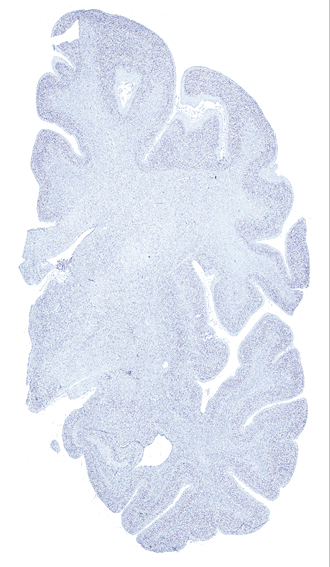

Hi-Resolution Sections · Cells (Nissl Staining) · Virtual Microscopy

Frontal sections (Nissl) from the Atlas Brain:

Slice ID:

r3-1082

Plate NR:

ca 28-29

Position:

8,5 mm